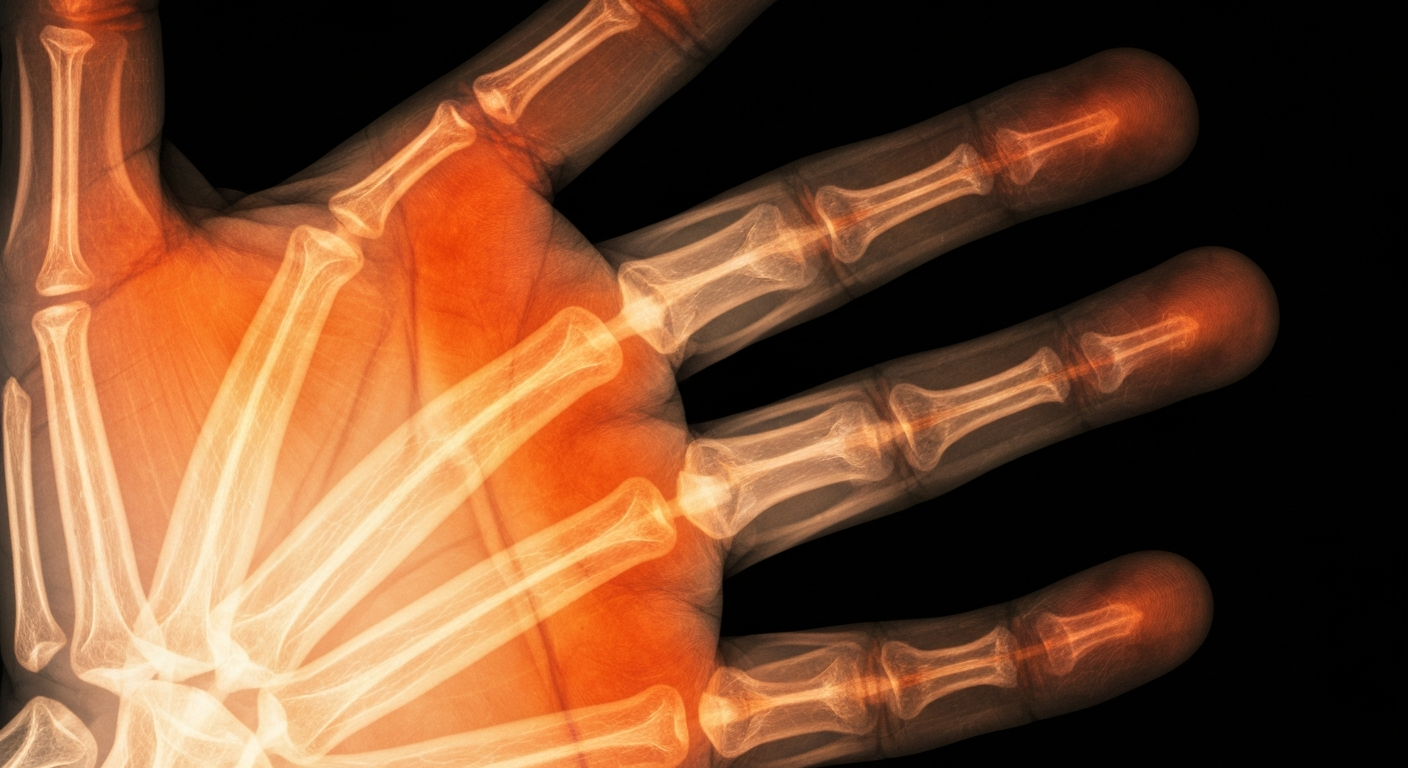

An X-ray view of a sunburned hand highlights the fragile nature of skin damaged by UV exposure.Salt Lake City TodayAs the weather heats up, sunburns are becoming more common. KSL medical contributor Phil Cowley shares his expert advice on which sunburn treatments actually work and which ones should be avoided, covering a range of options from hydrocortisone to aloe vera to ibuprofen.